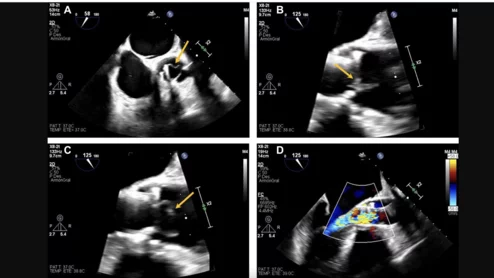

The new guidelines detail the use of echocardiography to evaluate patients for a variety of conditions.